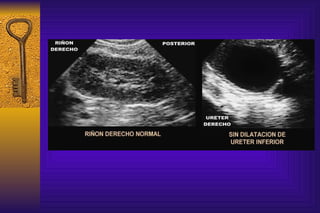

Como detectamos anormalidades de los riñones o de las vías urinarias La ecografia renal permite identificar la morfología renal  y es útil para establecer calidad de las vías urinarias. Permite observar cálices y la pelvis pudiendo medir los diámetros anteroposteriores y espesor del parénquima

Como detectamos anormalidadesde los riñones o de las vías urinarias La ecografia renal permite identificar la morfología renal y es útil para establecer calidad de las vías urinarias. Permite observar cálices y la pelvis pudiendo medir los diámetros anteroposteriores y espesor del parénquima